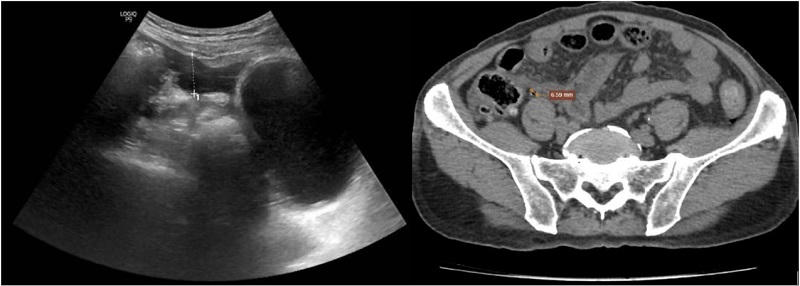

Kết quả chẩn đoán hình ảnh ghi nhận: Chụp X-quang có dấu hiệu liềm hơi dưới cơ hoành hai bên; Siêu âm có khí tự do ổ bụng, nghi thủng tạng rỗng vùng hành tá tràng; CT scanner ghi nhận nhiều dịch và khí tự do trong ổ bụng, hướng tới thủng tạng rỗng.